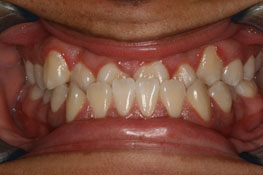

Invisalign Case in Progress – other orthodontist said Invisalign would not work. Invisalign always works in Dr. McCoy’s hands!

• Another orthodontist was talking jaw surgery and braces

• No surgery, just Invisalign by DesignTM with Dr. McCoy!

• Almost done. Just close some space and another happy patient is finished!

Before

After